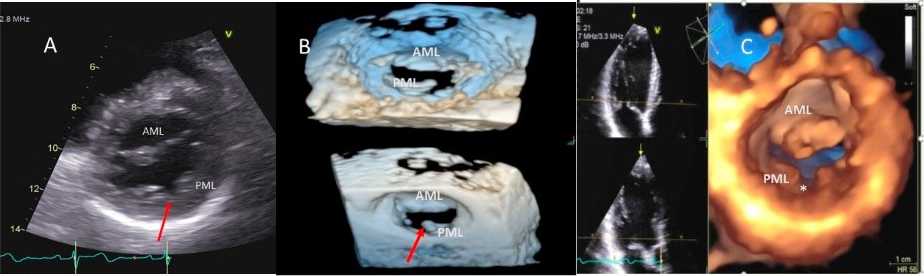

As opposed to degenerative MR, mitral valve leaflets in secondary MR may be normal but MR results from leaflet mal-coaptation due to a dilated mitral annulus as in dilated cardiomyopathy or due to tenting of mitral leaflets due to LV infarct remodeling causing outward displacement of papillary muscles and tethering of chordae attached to these papillary muscles. Mal-coaptation may be along the entire mitral leaflet coaptation plane mostly in functional MR (Fig. 3A–C) or localized to some scallops commonly seen at the P3 scallop of the mitral valve in the presence of a remodeled infero-posterior myocardial infarction causing tethering of the chordae to P3 scallop (ischemic MR).

Fig. 3.Functional Mitral regurgitation. (A) Transesophageal echocardiogram biplane view shows a dilated LV with mitral valve coaptation point displaced into the LV and central MR jet. (B) 3D TEE showing central mitral leaflet malcoaptation (white asterisks). (C) 3D TEE surgical view of the mitral valve showing severe central mitral regurgitation. LA, left atrium; LV, left ventricle; AML, anterior mitral.